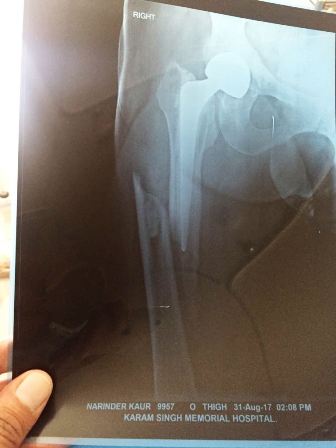

Patient : Mrs. Narinder Kaur

Age / Sex : 55 yrs Female

Procedure : Cemented Total Hip Arthroplasty with multiple circulage wiring

• A case of peri-prosthetic fracture femur.

• 15 yrs old Cemented Hemi-arthroplasty done.

• On x-ray appears simple fracture so planned non-cemented Total Hip Arthroplasty with wagner stem, whose size starts from 14 mm onwards.

• When we remove bipolar whole of femur open like a book up to distal 1/3rd.

• Now to remove cement becomes difficult and remove not joints.

• So decided for cemented Total Hip Arthroplasty with multiple circulage wiring.

• Now patient started walking without walker.